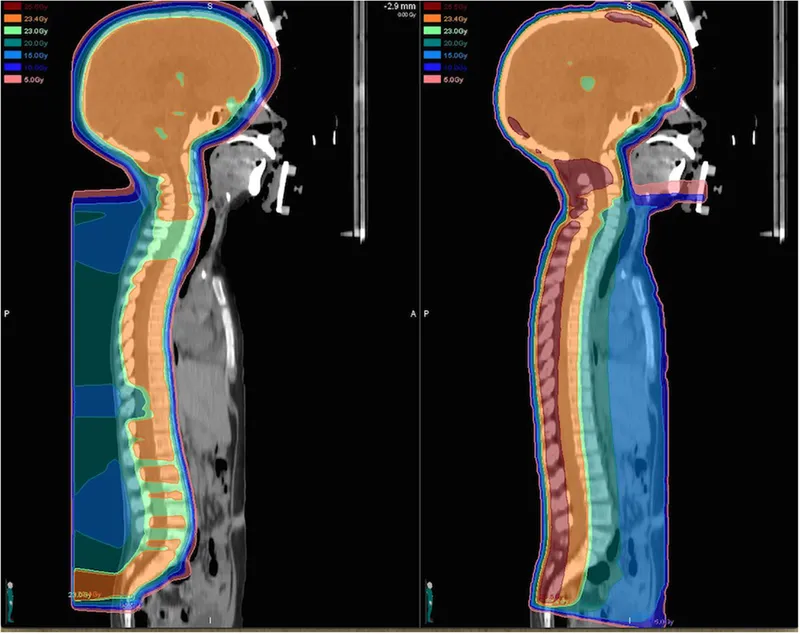

Radiation Therapy (RT): Uses ionising radiation to achieve local tumour control.

- Crucial for unresectable tumours, positive margins, or as definitive therapy.

- Principle: ALARA (As Low As Reasonably Achievable) to minimise damage to developing tissues.

- Proton Beam Therapy is preferred to spare normal tissues and reduce long-term toxicity.